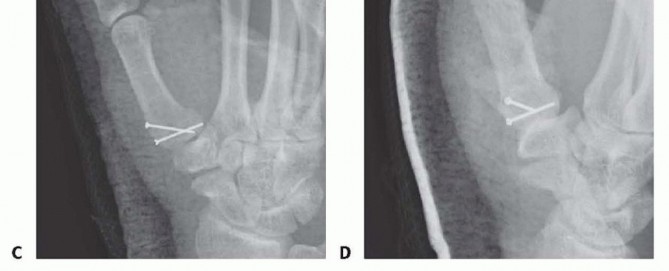

Closed Reduction and Percutaneous Pinning (CRPP)

CRPP is the treatment of choice for classic Bennett fractures where the volar-ulnar fragment is too small to reliably accept a lag screw, yet the joint can be anatomically reduced closed. The reduction maneuver is highly specific, designed to counteract the deforming forces of the APL and Adductor Pollicis. Longitudinal traction is applied to the thumb, followed by palmar abduction and pronation. Direct pressure is then applied to the dorsal-radial aspect of the metacarpal base, effectively pushing the shaft back into the anatomic cradle of the intact volar-ulnar fragment.

Once anatomic reduction is confirmed via multi-planar fluoroscopy, percutaneous fixation is achieved. Typically, two 0.045-inch or 0.062-inch Kirschner wires are utilized. The first wire is driven from the dorsal-radial aspect of the metacarpal shaft directly into the trapezium, effectively neutralizing the proximal pull of the APL. A second wire is often placed transversely from the first metacarpal shaft into the second metacarpal to control rotation and maintain the web space. Pins are cut outside the skin and capped to facilitate easy removal in the clinic.

Image